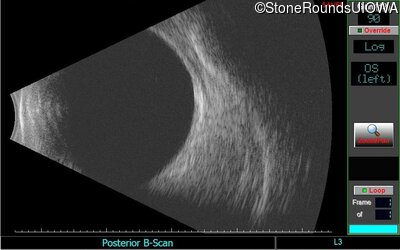

B-Scan Ultrasonography - Left - 20/30 +2

Exemplar